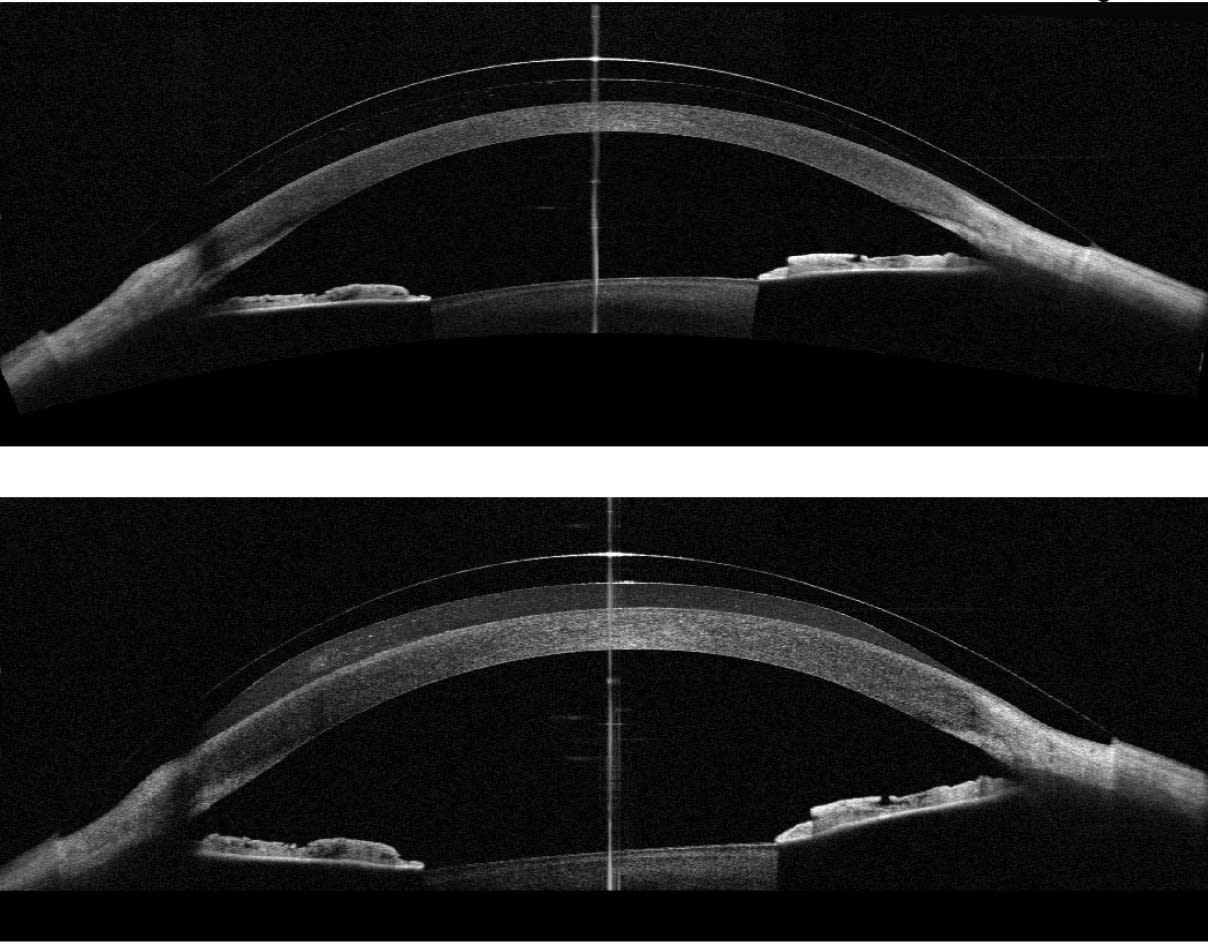

Dr. Lotoczky shared a clinical image (Figure 1) that emphasizes the need for further research on scleral lens wear.

“Throughout the 8 hours of wear, the lens appears to have mildly compressed the conjunctiva, and we see a difference in the lens clearance,” says Dr. Lotoczky of the image. “In addition, visible changes can be observed with the naked eye in the position of the iris and crystalline lens, as well as in the anterior chamber angle. Further research is needed to determine why these changes occur in some patients—whether they are driven by suction forces, mechanical effects, or a combination of both.”